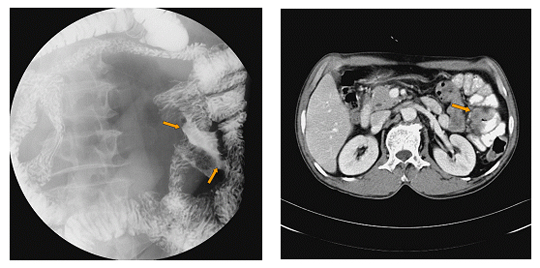

소장조영검사(small bowel series)는 소장의 종양성 병변을 진단하는 방사선학적 검사 중 가장 중요한 검사입니다. 소장조영검사에는 두 가지 방법이 있는데, 경구 소장조영술과 고위 관장법(enteroclysis)입니다.

경구 소장조영술은 조영제(주로 바륨 현탄액)를 마시고 일정한 간격으로 복부 단순 방사선 촬영 사진을 촬영하는 방법으로 일반적으로 소장조영검사라 하면 이 방법을 말합니다. 경구 소장조영술은 50%-80%의 정확도를 보입니다.

고위 관장법은 코를 통해서 십이지장이나 근위부 공장까지 직접 관을 삽입한 후 이 관을 통해 조영제를 소장에 직접 투여하여 단순 방사선 촬영 사진을 촬영하는 방법입니다. 이 방법은 정확도가 90% 내외지만 검사가 힘들고 방사선 조사량도 상대적으로 많습니다.

복부의 전산화단층촬영검사를 통해서 소장 종양의 복강 내 위치를 파악할 수 있습니다. 또한 전산화단층촬영 검사는 종양의 침윤 정도나 간 전이 같은 소장 외 병변의 진단에도 유용합니다. 특히 소장 내 종양이 양성인지 악성인지도 예측할 수 있습니다.

[ 소장(공장)암의 소장조영검사 소견 및 전산화단층촬영 소견 ]